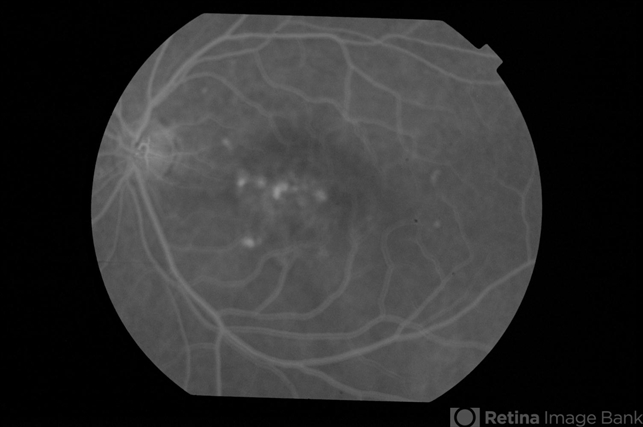

- CSCR subfoveal leak

- 52-year-old male with left eye CSCR of 6 months duration. Early phase fluorescein angiogram shows multiple leaks including a sub-foveal one. He was treated with PDT with complete resolution of fluid.